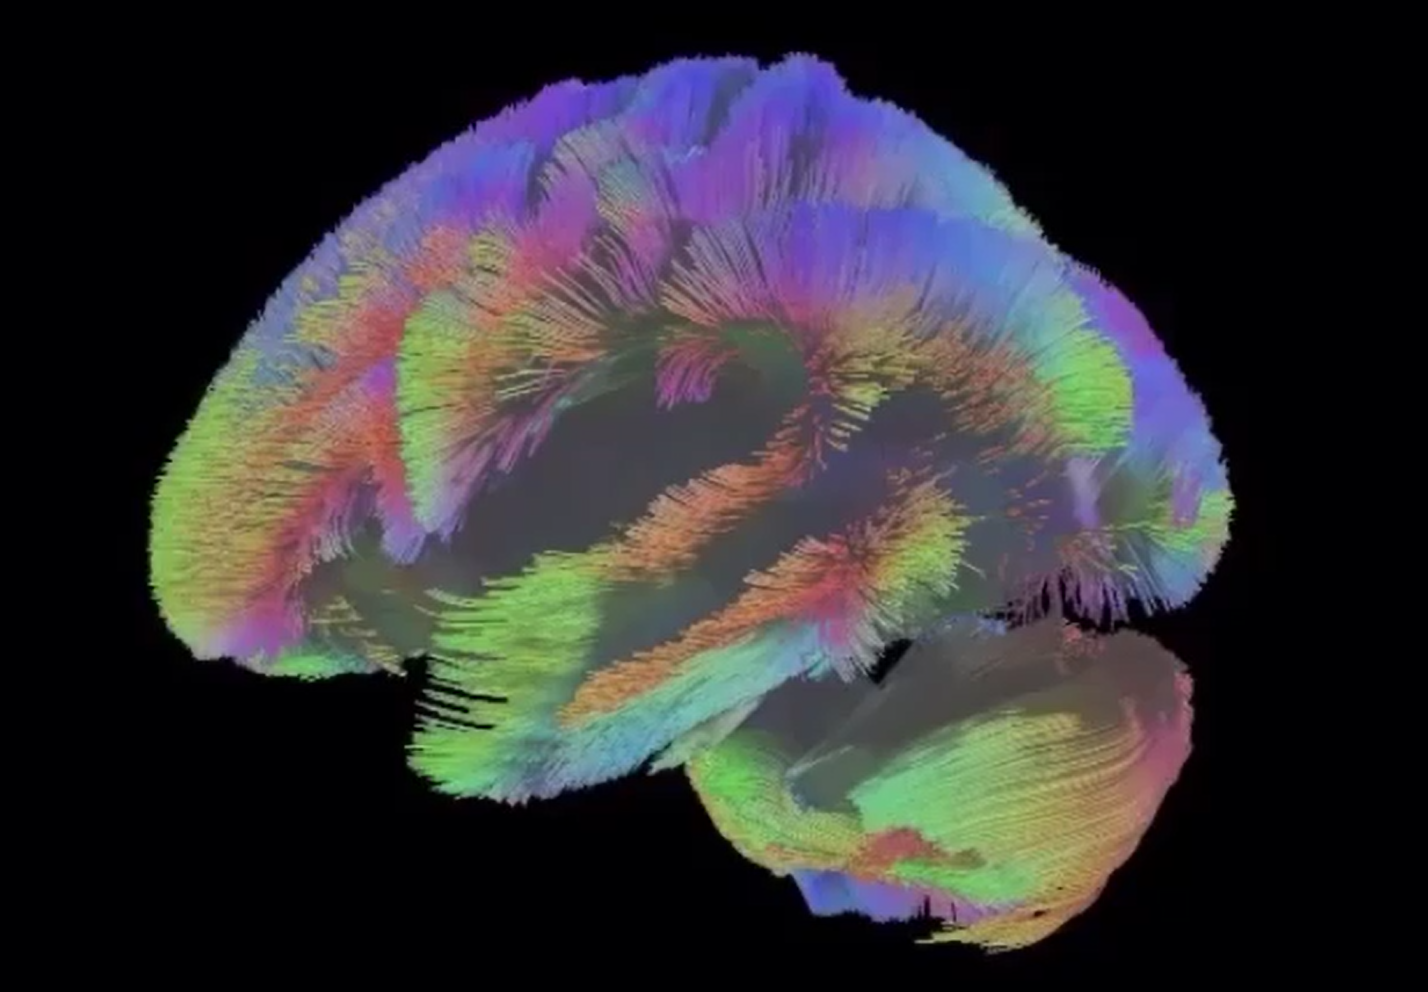

Diffusion Tensor Imaging (DTI) - Fiber Tracking - Imagilys

Diffusion Tensor Imaging (DTI) - Fiber Tracking - Imagilys

Diffusion Tensor Imaging (DTI) revealing connectivity in the brain

Diffusion Tensor Imaging (DTI) - Fiber Tracking - Imagilys

Using Diffusion Tensor Imaging (DTI), axonal fiber tractography

Diffusion Tensor Imaging (DTI) – Department of Medical Physics

Diffusion tensor imaging and fiber tractography | Radiology